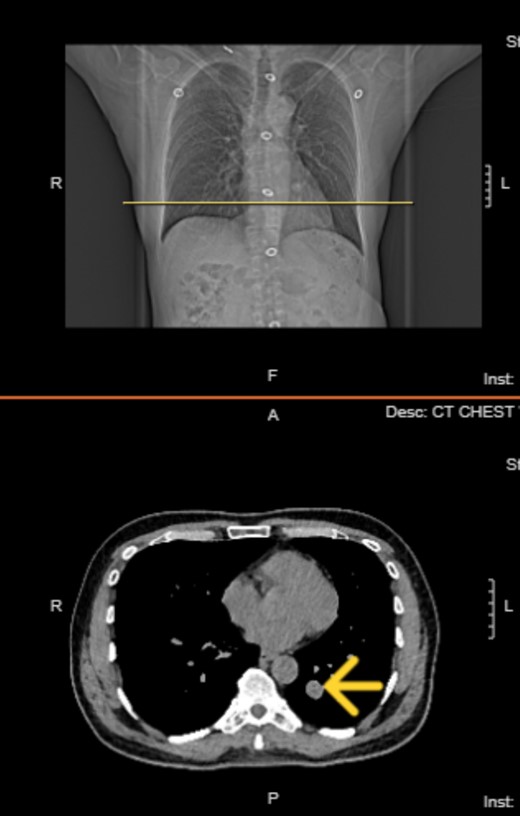

Upon diagnosis of SFT, the patient was referred to a surgeon for consideration for left lower wedge resection via video-assisted thoracoscopic surgery. However, the treatment consisted of monitoring of the tumor with biannual CT scans. Immediate surgical intervention was not performed, as the tumor remained stable in size, asymptomatic, and showed no signs of aggressive behavior. The latest CT on 30 January 2024 shows the tumor size to be 1.9 × 1.6 cm (initial size 1.5 × 1.3 on 21 May 2021) with no accompanying symptoms (Figs 2 and 3).

Chest computed tomography in 2024 shows well circumscribed solitary lung tumor of 1.9 × 1.6 cm in size.

Top image: Coronal view indicating the level of the solitary fibrous tumor (SFT). Bottom image: Axial CT scan at the indicated level, showing a well-circumscribed, homogeneous mass.